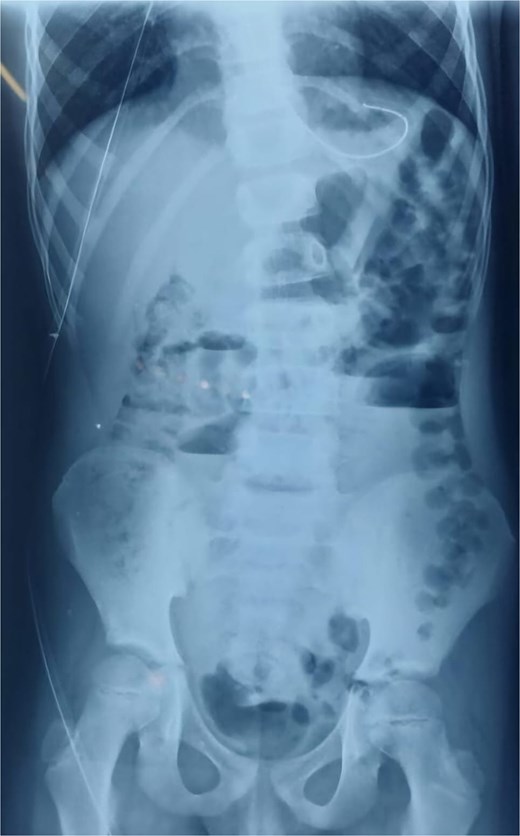

An abdominal X-ray showed multiple dilated bowel loops with air-fluid levels (Figs 1 and 2), consistent with a high-grade intestinal obstruction. Given the patient’s surgical history, a diagnosis of volvulus secondary to intestinal malrotation was strongly considered.

X-ray image after 6 h of admission, showing persistence of air-fluid levels.